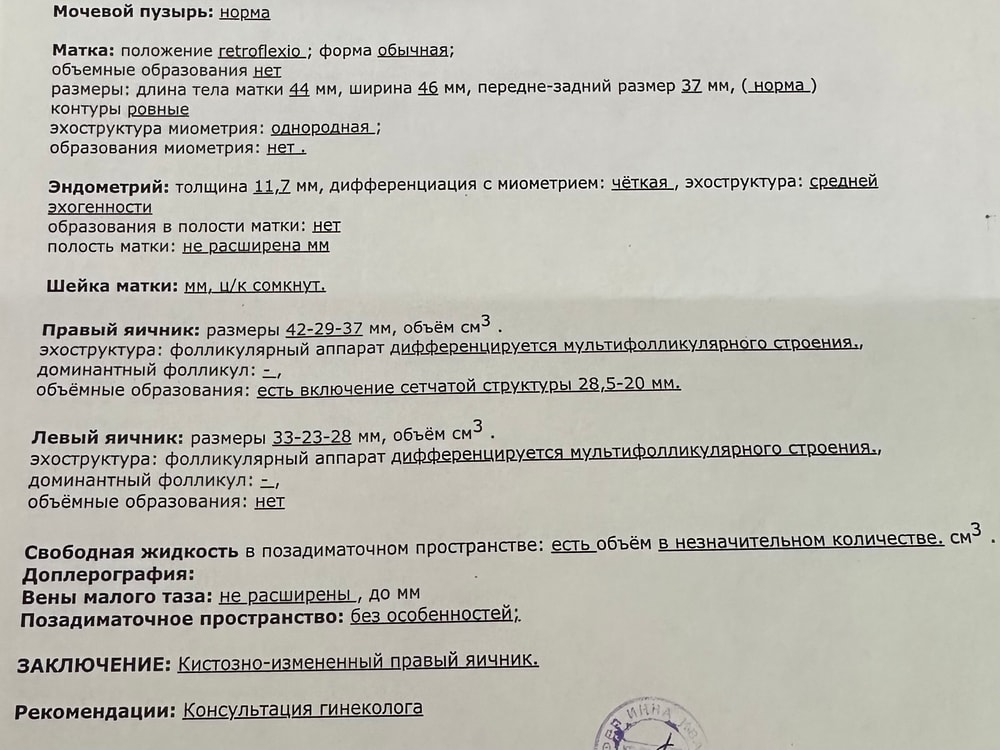

Может кто-то разбирается в узи? Не знаю какая это киста.

Рыдаю, просто, в голос! Устала! Как же я устала! Всего 2 овуляции за год, одна из них стимулированная. 5 лет 5 мес и 12 дней, как мы с мужем решили что готовы стать родителями. Отмена кок. Знаете, это когда встречаешь грустные новости от знакомых, в интернете и думаешь «нет! Со мной такого никогда не произойдет».